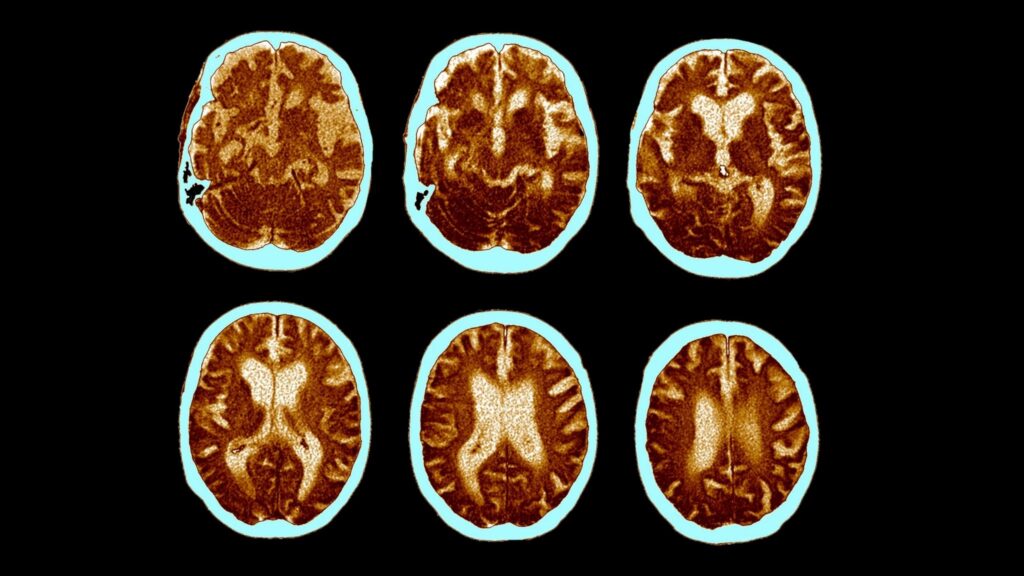

A IA comparou os exames com um banco de dados de mais de 3.600 imagens cerebrais, reconhecendo padrões típicos de doenças como Alzheimer, demência por corpos de Lewy e demência frontotemporal.

Um dos diferenciais da tecnologia é a geração de mapas digitais coloridos que destacam as áreas do cérebro comprometidas, facilitando a análise mesmo para médicos que não são especialistas. Além disso, os exames puderam ser interpretados quase duas vezes mais rápido em comparação ao método tradicional.